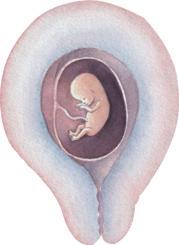

Befruchtung: eine Samenzelle dringt in eine Eizelle ein.

Abb. 2: eindringendes Spermium in die Eizelle der Frau

Die Spermien können an den fruchtbaren Tagen durch die Gebärmutter zur Eizelle in den Eileiter schwimmen. In dieser Phase kann die reife Eizelle mit einer Samenzelle verschmelzen. Durch den Vorgang der Befruchtung ist ein neues menschliches Leben entstanden. Die befruchtete Eizelle kann nun mit der Gebärmutterschleimhaut verwachsen. Diesen Vorgang nennt man Einnistung

Abb. 1: Phase zwischen 14. und 16. Zyklustag und Befruchtung einer Eizelle